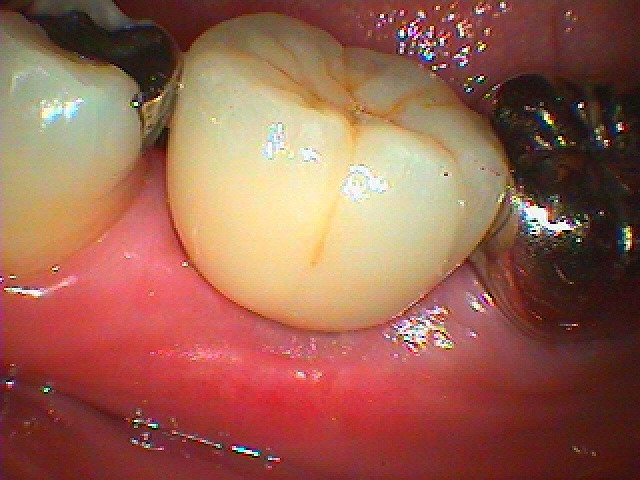

インプラント埋入後2か月を経てインプラントの上部構造を建てていきます|お知らせ |広島市安佐南区の歯科医院 インプラント埋入後2か月を経てインプラントの上部構造を建てていきます トップ お知らせ・ブログ お知らせ インプラント埋入後2か月を経てインプラントの上部構造を建てていきます インプラント埋入後2か月を経てインプラントの上部構造を建てていきます 術後のパノラマになります このようにきれいに傷がいえています 歯肉形態を付与していきました このような上部構造を入れていきました 口腔内に入ったところになります ソーサライゼーションはありますが、、 このように綺麗に仕上がっています Web診療予約 初めての方へ 選ばれ続ける理由 院内設備について 歯が痛いしみる一般歯科 歯がぐらぐらする歯周病 健康な歯を保ちたい予防歯科 子供の虫歯予防をしたい小児歯科 銀歯をセラミックに審美歯科 白い歯を目指しませんか?ホワイトニング 矯正専門医がいるので安心矯正歯科 抜けた歯を補いたいインプラント・入れ歯 医院案内 スタッフ紹介 メリィハウス歯科クリニックオフィシャルホームページ ラベンダー歯科クリニックオフィシャルホームページ お知らせ・ブログ ホーム 診療科目 一般歯科 歯周病治療 予防治療 小児歯科 審美治療 ホワイトニング 矯正歯科 入れ歯・インプラント マウスピース矯正 初めての方へ 院長・スタッフ 設備紹介 医院案内・アクセス メニューを閉じる